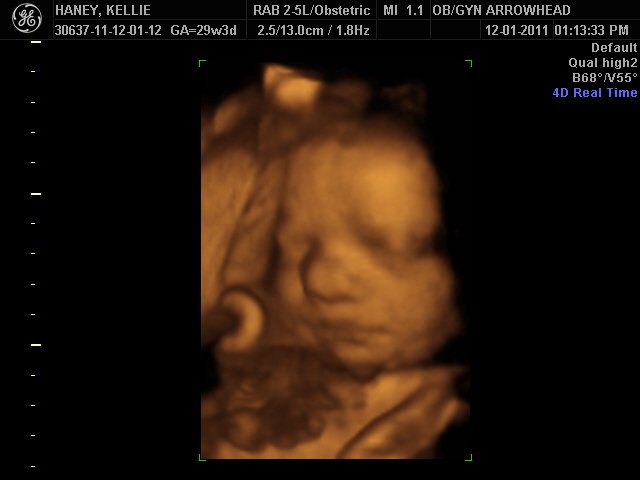

We offer complimentary 3D/4D Ultrasounds to all our OB patients around 30 weeks! The following photos are some examples of our work, shown with permission from our patients.